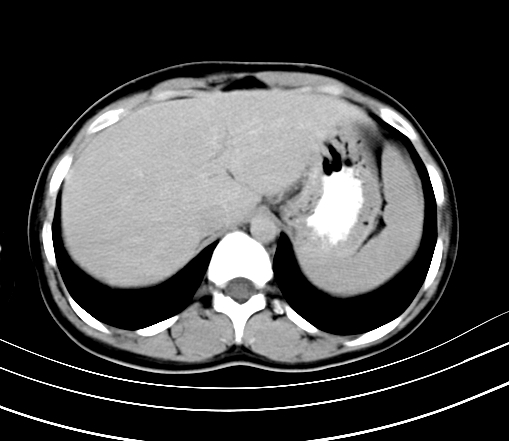

动脉期